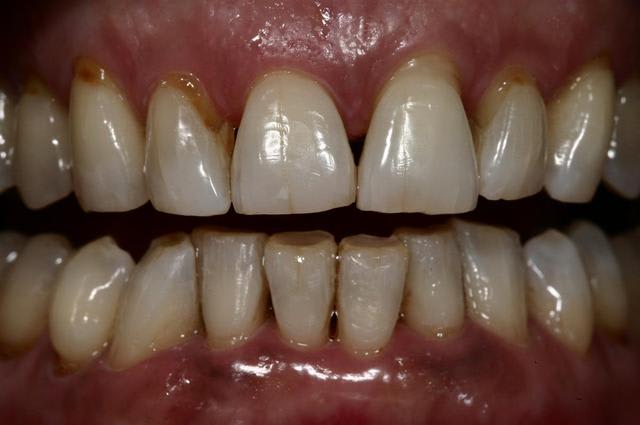

pour terminer avec ma patiente qui initia ce post:

aprés blanchiment.